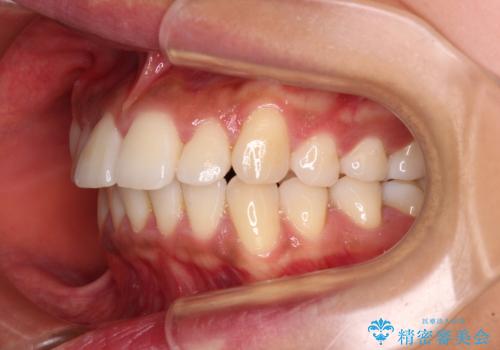

カリエール・ディスタライザーを併用したインビザライン矯正治療

カリエールディスタライザーを併用したことで、確実かつ短期間で治療を終えることができました。

- 全体的な歯列の叢生を気にして来院された患者様です。

奥歯の咬み合わせを見ると、片方は上顎が下顎に対して相対的に前方にある状態でした。

咬み合わせを改善するためには、上顎臼歯を後方に移動させた咬み合わせにする必要があります。

インビザライン単体で改善することも可能ですが、ディープバイトのためインビザライン単体で達成する可能性が低いと考えられたため、カリエール・ディスタライザーという補助装置を併用して、より確実性を上げることとしました。

奥歯の咬み合わせ改善後に、インビザラインにて歯列を整えることとしました。